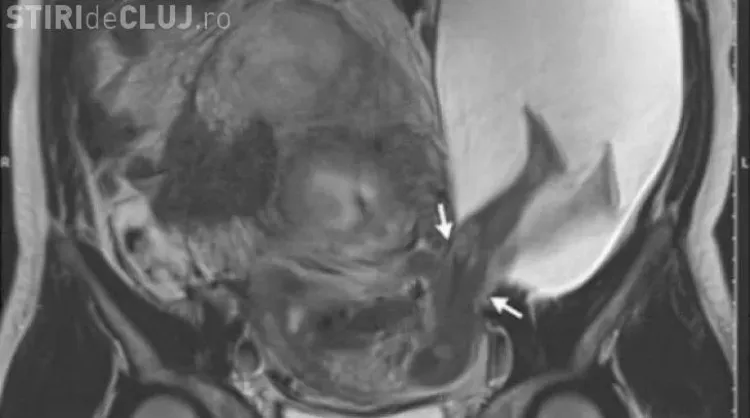

Ecografia din cea de-a 22 săptămână de sarcină a dezvăluit o problemă rară medicală. Din cauza faptul că mai adusese pe lume încă cinci copii, membrana uterului ei se subţiase foarte mult astfel că, la cea de-a şasea sarcina, această nu a mai rezistat tensiunii şi a cedat pe o porţiune de 2.5 centimetri.

Picioarele bebeluşului au ieșit din sacul amniotic, iar sarcina s-a complicat astfel foarte mult.